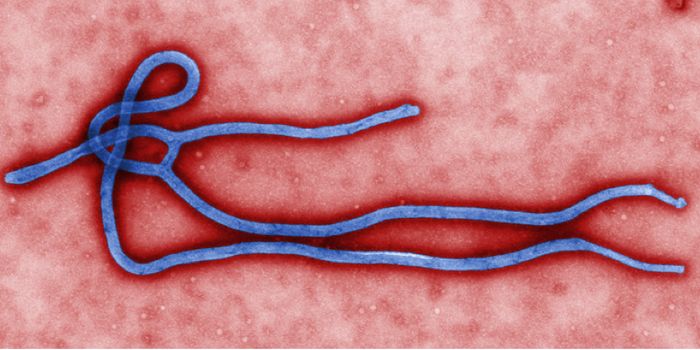

MAR 04, 2016Clinical & Molecular DXA new small-molecule drug was recently shown to protect Rhesus monkeys from the Ebola virus, decreasing viral loads sign ...